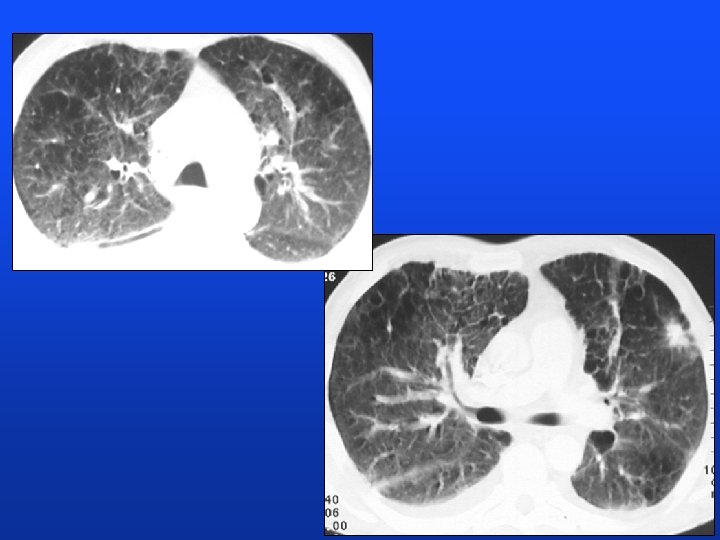

HRCT

CT 2. 11. 2000

CT, brain 3. 11. 2000 Autopsy: lung CA, carcinomatous lymphangiopathy, non-infectious (marantic) endocarditis, peripheral embolization